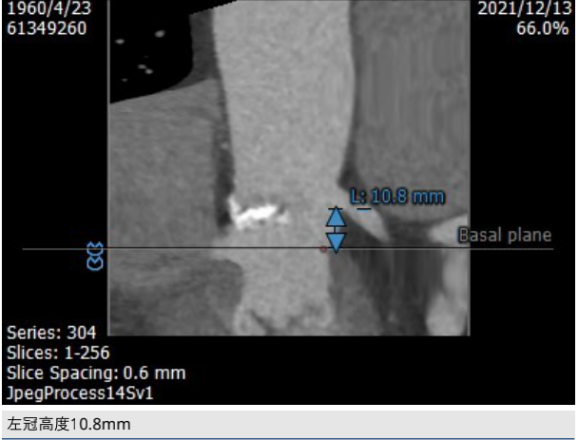

CT评估: